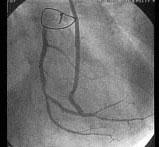

图中冠状动脉造影结果为 ( )A、右冠近端95%狭窄B、桥血管显像C、右冠远端95%狭窄D、左冠回旋支95%狭窄E、左主干近端95%狭窄

问题 图中冠状动脉造影结果为 ( )

选项 A、右冠近端95%狭窄 B、桥血管显像 C、右冠远端95%狭窄 D、左冠回旋支95%狭窄 E、左主干近端95%狭窄

答案 B